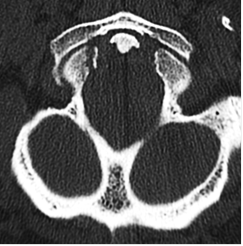

Figures ci-dessus : Accident de moto sur circuit, intubation sur place. Le body-scanner révèle un hématome sous dural supra-tentoriel gauche, de multiples petites contusions cérébrales hémorragiques, une fracture isolée du condyle occipital droit, une contusion du rein gauche avec lame d’hématome sous capsulaire.